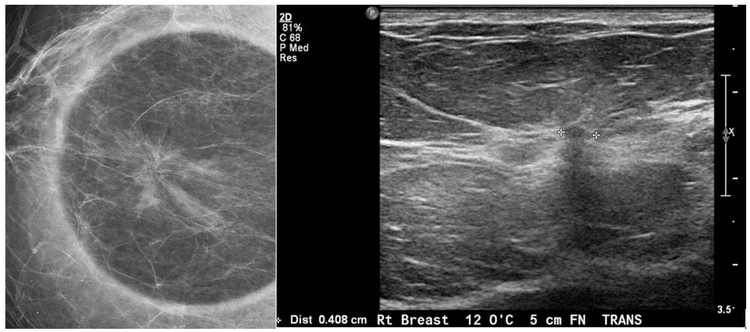

Bài viết bởi Thạc sĩ, Bác sĩ Tống Dịu Hường – Khoa Chẩn đoán hình ảnh – Bệnh viện Đa khoa Quốc tế Vinmec Nha Trang Sẹo tỏa tia là một bệnh lý tăng sinh lành tính của vú. Các nguyên nhân có thể được đề xuất bao gồm phản ứng viêm tại chỗ và […]